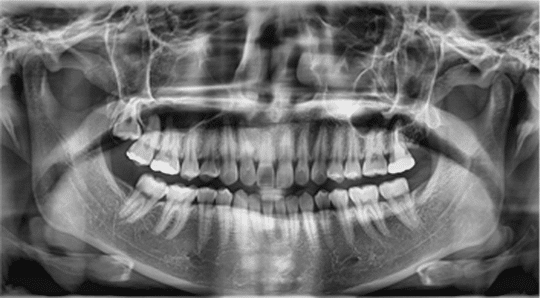

Below are some screen images of the information we gain that is invaluable to the dental Implant process as it allows to visualise the placement in 3D. The main benefit is that as we know the anatomy of the site where the implant is placed we do not have to make large cuts(incisions) in the gum. Implants are placed through a very small hole in the gum therefore reducing healing time and post surgery discomfort and swelling.

When to scan a patient

The criteria are as follows:

- Single teeth implants in areas near delicate anatomical structures.

- Mandibular Implants near I.D. or mental nerve.

- Multiple immediate Implants.

- Work involving full arch or multiple unit Implant work.

- Before Sinus Lifting or Grafting.

- Before Grafting procedures.

- Nerve Repositioning surgery.

- For Computer Aided Placement Stents e.g. Nobel ® guide, Materialise ® Guides (Belgium).